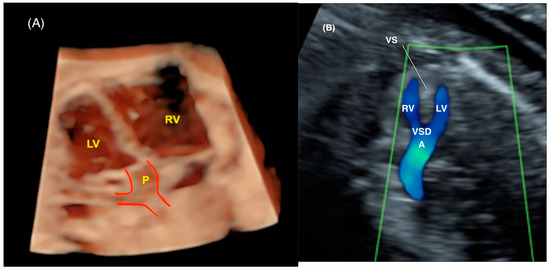

- Liu, J.; Wang, Y.; Zhao, H.; Liu, W. Spatio-temporal image correlation rendering mode visualizes the specific location and surrounding structure of ventricular septal defect. Clin. Anat. 2019, 32, 408–420. [Google Scholar] [CrossRef]

- Rizzo, G.; Capponi, A.; Vendola, M.; Pietrolucci, M.E.; Arduini, D. Role of tomographic ultrasound imaging with spatiotemporal image correlation for identifying fetal ventricular septal defects. J. Ultrasound Med. 2008, 27, 1071–1075. [Google Scholar] [CrossRef]